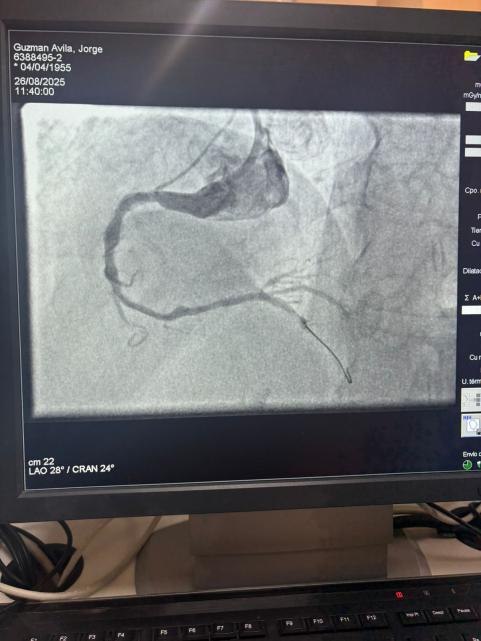

Estamos orgulhosos de compartilhar um caso notável do Hospital Sótero del Río, Chile, onde o Dr. Martín Valdebenito tratou com sucesso uma lesão fortemente calcificada na artéria coronária direita (primeira curva) usando nosso Sistema de Cateter de Dilatação Coronária Vesscrack.

O procedimento alcançou excelentes resultados, com a região calcificada efetivamente rachada e o fluxo do vaso restaurado. Isso marca outro marco na expansão do acesso global a soluções avançadas para calcificação coronariana complexa.

A comparação entre as imagens angiográficas pré-procedimento e pós-procedimento demonstra claramente o impacto clínico significativo de nossa tecnologia IVL.